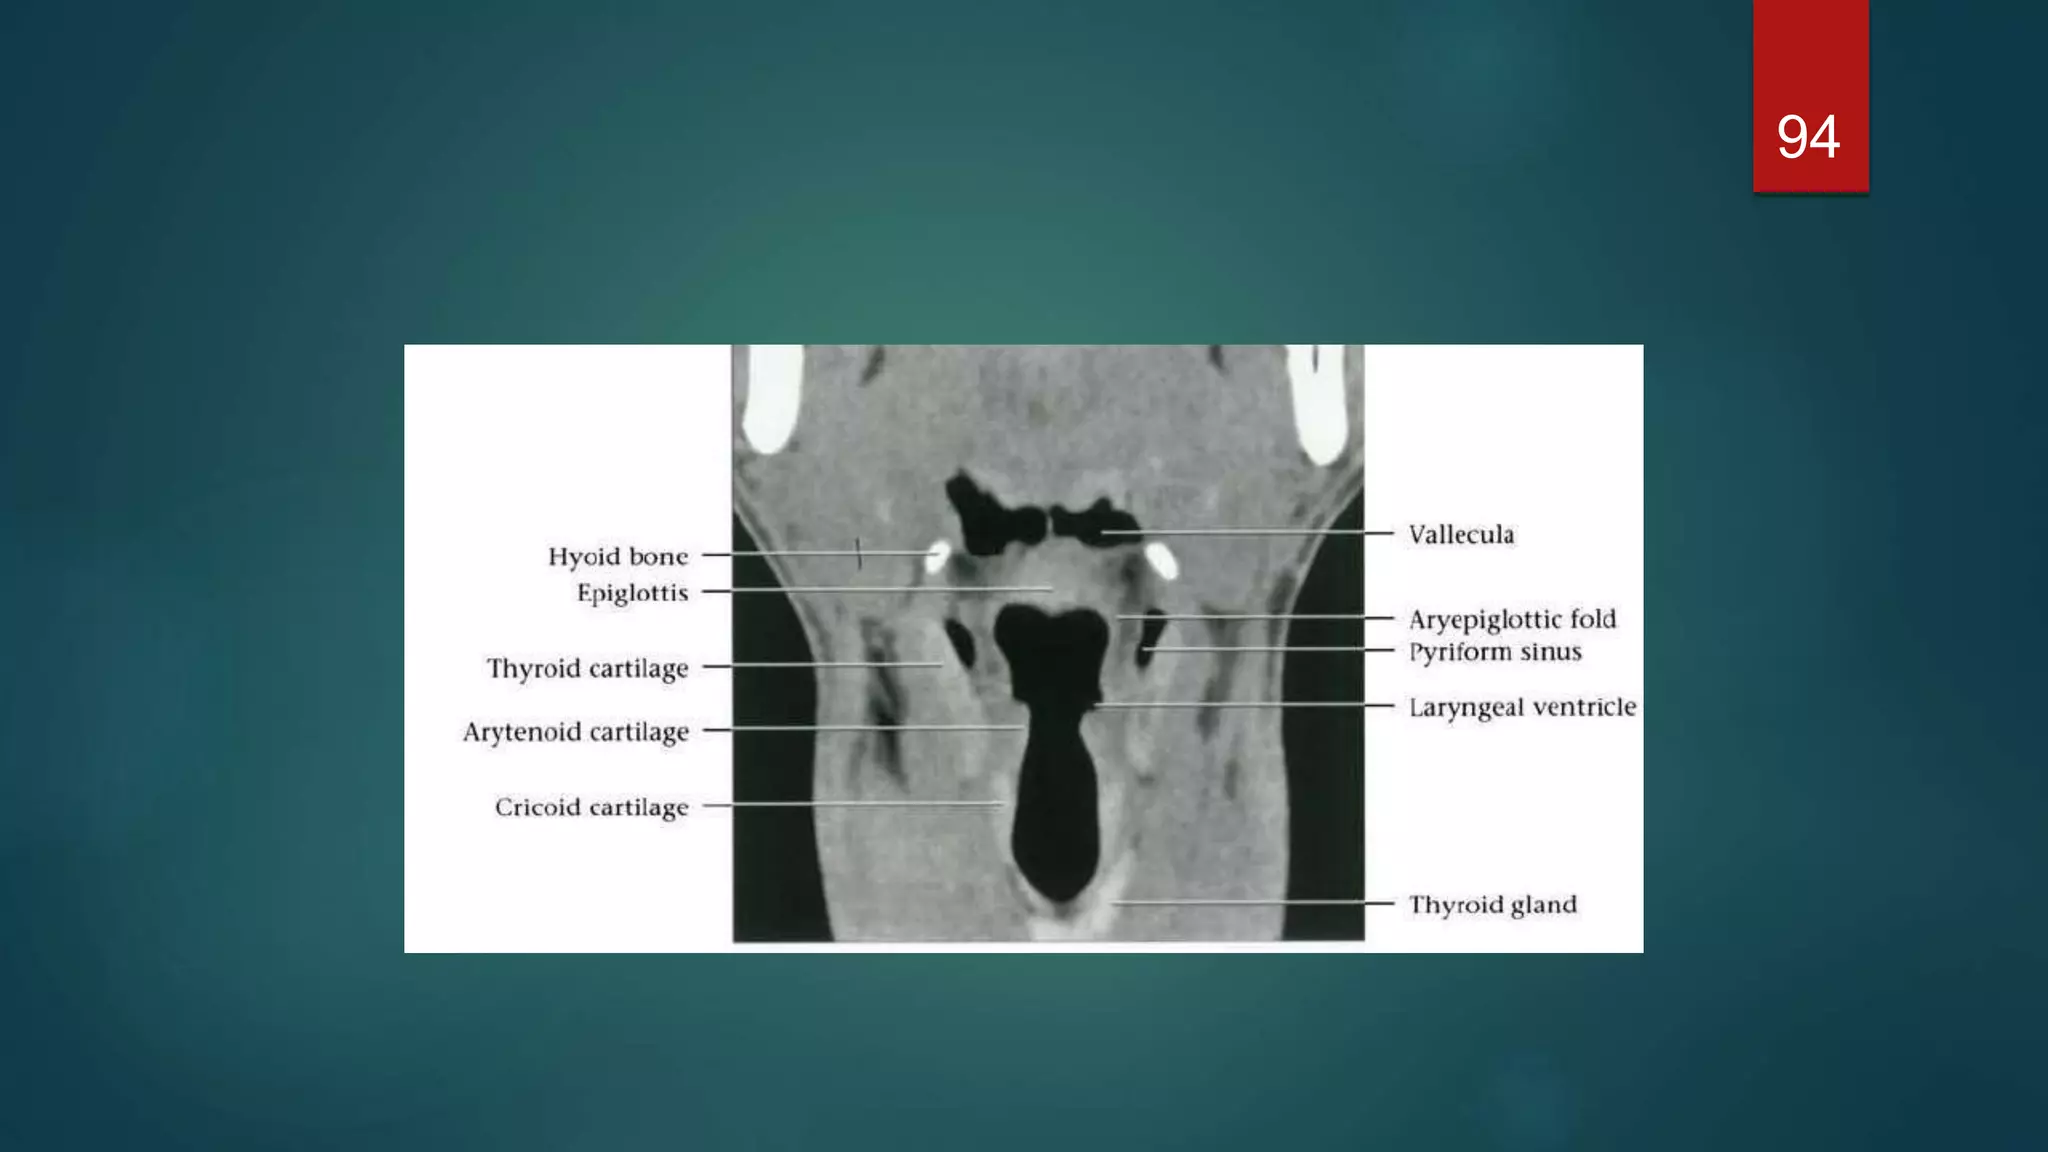

 The epiglottisis a leaf-shaped cartilage whose narrow base is attached to the inner surface of the thyroid cartilage  It projects up behind the base of the tongue and directs boluses laterally into the piriform fossae during deglutition, thus protecting the larynx.  Three mucosal folds, the glossoepiglottic folds - namely, a central and two lateral folds - pass from the anterior surface of the epiglottis to the base of the tongue. These form paired recesses between the base of the tongue and the epiglottis known as the valleculae.  A further pair of mucosal folds pass from the lateral margin of the epiglottis posteriorly to the arytenoid cartilages separating the larynx from the piriform fossae. These are the aryepiglottic folds which, together with the epiglottis, define the entrance to the larynx.  The cavity of the larynx is divided into three parts by upper and lower pairs of mucosal folds. The upper pair of folds are the false cords. The space between the laryngeal entrance and the false cords is known as the vestibule or the sinus of the larynx.  The lower pair of folds are the true cords and contain the vocal ligaments, which are responsible for voice production. The space between the false and true vocal cords is the laryngeal ventricle. 70

Cross-sectional anatomy ofthe larynx Supraglottic level  The larynx is anterior to the piriform sinuses, separated from them by the aryepiglottic folds. 71

Glottic level  Acomplete ring of cartilage is seen at this level –thyroid cartilage anteriorly & lamina of the cricoid &arytenoid cartilages posteriorly.  The anterior fusion of the vocal cords is known as the anterior commissure and is very thin when the cords are abducted. Similarly, the posterior commissure, which is seen between the arytenoids  The larynx is elliptical in shape at the level of the true cords and triangular at the level of the false cords, which are at a slightly higher level. 74

Infraglottic level  Justbelow the cords the larynx is elliptical. The lamina of the cricoid is posterior, with the cricothyroid membrane anterior.  At a lower level the larynx is more circular and the cricoid forms a complete ring. Part of the lobes of the thyroid gland may be seen laterally, 76